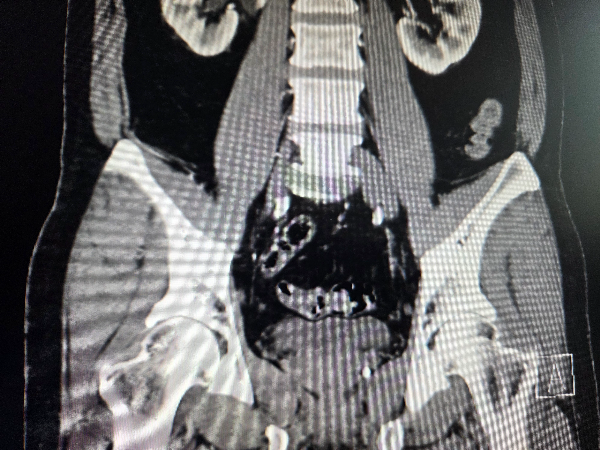

2. 엑스레이 CT촬영

진통제가 들어가면 통증이 조금은 아주 조금은 줄어들기 때문에 빠르게 엑스레이와 CT촬영을 했습니다.

엑스레이는 금방 촬영하고, CT는 5분 정도 소요됩니다.

요로결석 진단 결과

요로관에 3mm의 결석이 있고, 신장안에도 더 작은 사이즈의 결석이 하나 더 있다고 합니다.